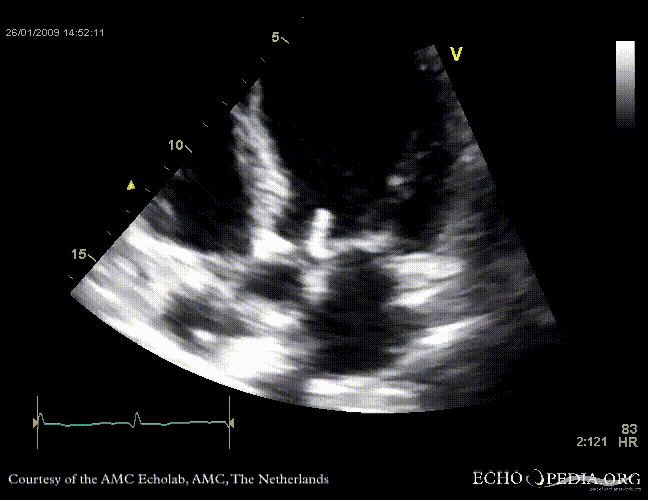

Aortic valve endocarditis with vegetation

Case description: This patient had endocarditis with an aortic valve vegetation

E00117.gif E00119.gif

PLAX aortic valve vegetation A3CH aortic valve vegetation